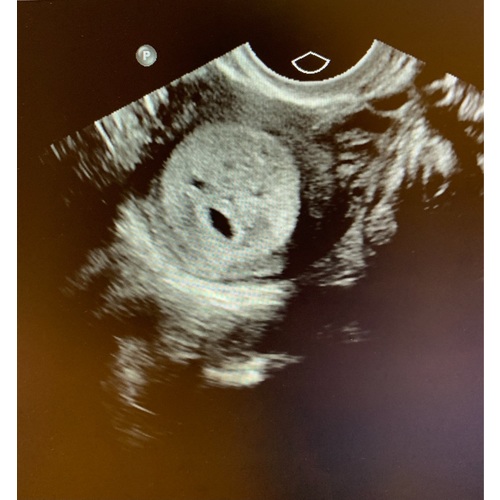

Hai hai, ik heb gisteren een echo laten maken in Erasmus (5w2d). Dit was een vroege echo omdat ik 3x een miskraam heb gehad. Wij hadden ons erop voorbereid dat we weinig zouden zien... maar dit was ook zo... als je heel vroeg een echo gaat maken kun je enkel uitsluiten dat het niet om een bbz gaat. Met een beetje geluk zie je al meer maar als je niets ziet kan dat juist ook heel onzeker maken... Zou proberen om het toch nog heel even uit te stellen... hoe spannend het ook is馃槄馃槄馃槄馃槄馃ゴ馃ゴ

Dan zitten we op 6+5

Ze adviseren om het te doen vanaf 6+3 ivm het kloppen van het hartje. Dan heb je meer zekerheid ipv dat je het straks op 6w doet